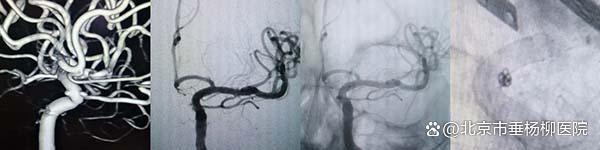

病例2:三微导管技术,支架辅助弹簧圈栓塞宽颈分叶状动脉瘤

韩女士诊断为左侧颈内动脉眼动脉段破裂宽颈分叶状动脉瘤,团队采用“三微导管”技术,动脉瘤内放置两根微导管,交替分区填塞弹簧圈,第三根微导管放置于载瘤动脉内用于释放支架,实现致密栓塞。